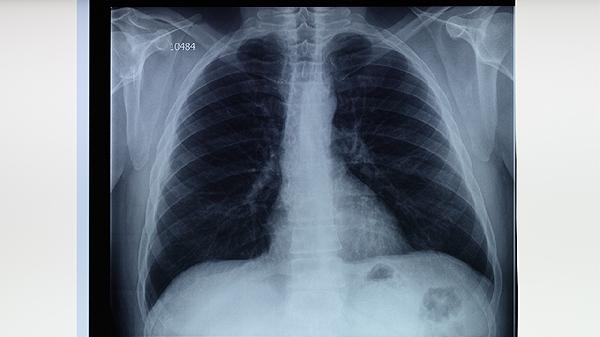

和肺结核病人说话了会不会传染

与肺结核患者交谈存在传染风险,但实际感染概率受接触距离、时间、患者传染性及自身免疫力等因素影响。肺结核主要通过飞沫传播,预防措施包括保持通风、佩戴口罩、避免密切接触等。